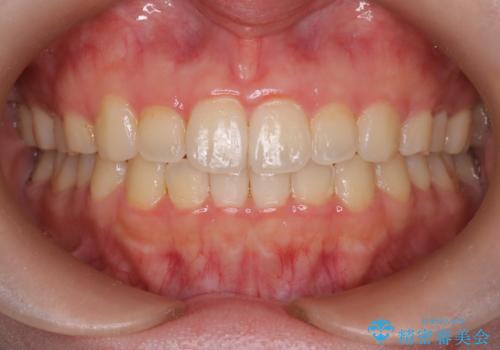

- 患者様は、下顎両側の第1大臼歯(6番)と右上6番の欠損を主訴に来院されました。

通常であればインプラントによる補綴が第一選択となる症例でしたが、患者様ご自身がインプラントを希望されなかったため、矯正治療によって欠損部の閉鎖を図る方針としました。

同時に、親知らず(智歯)の萌出や位置も考慮し、咬合全体のバランスを改善する矯正治療計画を立案しました。

ワイヤー矯正を用いて、欠損部の閉鎖を目的とした後方からの歯の挺出・移動を行いました。

特に、親知らずを活用し、奥歯の噛み合わせを構築することに重点を置きました。

最終的には予定通りインプラントを使用せずに欠損部を閉鎖し、咬合も安定させることができました。